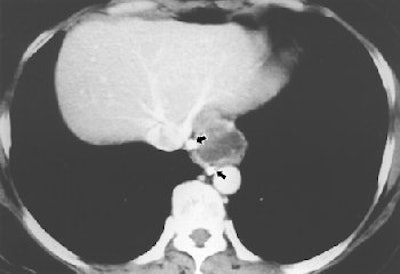

![]() |

| Fifty-year-old woman with submucosal tuberculous abscess in esophagus. Contrast-enhanced axial CT scan shows relatively well-marginated cystic mass at distal esophagus. Thick, partially calcified enhancing rim is noted at periphery of mass. Calcified small periesophageal lymph nodes (arrows) are adjacent to mass. Lee KH, Kim HJ, Kim KH, Kim HG, "Esophageal Tuberculosis Manifesting as Submucosal Abscess," (AJR 2003; 180: 1482-1483). |

Line scan diffusion-weighted MR images, as well as contrast-enhanced CT and esophageal endosonogram, can be used for diagnosis and evaluation of esophageal tuberculosis, which is relatively rare and found in less than 1% of patients who die of TB (AJR, May 2003, Vol. 180:5, pp. 1482-1483).